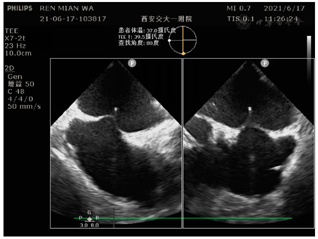

入院后常规检查未见明显异常,心动超声提示左房增大伴二尖瓣中量反流,LA前后径40mm。该患者入院后根据CHA₂DS₂-VASc评分及HAS-BLED评分来进一步评估其卒中及出血风险,该患者CHA₂DS₂-VASc评分4分,HAS-BLED评分3分,属于高卒中及高出血风险患者。因该患者仍有心悸症状发作,且多次服用抗凝药物后有上消化道出血表现,故向患者及家属建议行房颤射频消融及左心耳封堵一站式手术。术前进一步行食道超声明确左心耳是否存在血栓及形态,术前食道超声提示心耳内未见血栓,心耳偏小,在90°上可能呈反鸡翅型(表1)。

由于该患者术中需要精确房间隔穿刺,因此采用常规全麻+TEE指导术式,TEE指导下选择了偏下、偏前的房间隔穿刺部位(图5)。